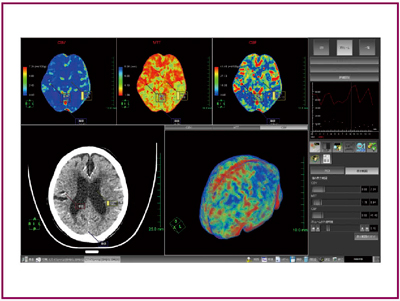

●頭部ボリュームパフュージョン

CTの多列化によって一度に撮影できる領域は大幅に広がり,頭部,呼吸器,循環器などのさまざまな領域でその性能が発揮され,進歩を続けている。特に頭部領域では,脳全体を一度に撮影することが可能となり,脳全体の四次元画像が容易に得られるようになった。そして,従来は1枚,あるいは特定の領域だけで行われていた頭部パフュージョン解析を全脳で行うことが可能になり,AZE VirtualPlaceの頭部パフュージョンも,従来のシングルスライスの解析に加えて,脳全体の領域の解析が行えるように機能向上が図られた(図6)。ユーザーは,対象画像を読み込んで解析実行ボタンをクリックするだけで,脳全体のパフュージョン解析を行うことができる。古くから急性期の脳梗塞などの評価に役立てられている頭部パフュージョンであるが,今後はより広い領域を解析することにより,的確な病変観察に役立つと思われる。

図6 頭部ボリュームパフュージョン画面